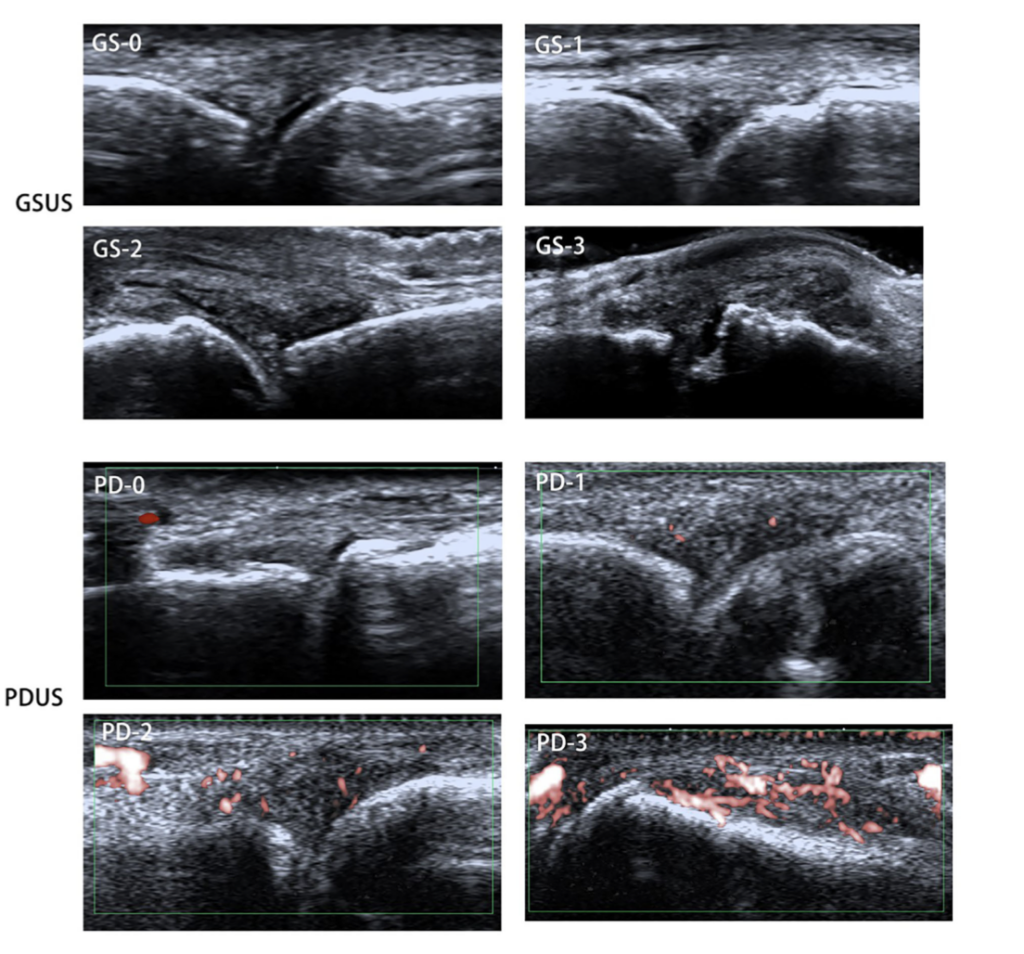

これはエコー画像をもとに滑膜炎の程度を0から3の4段階で評価する標準化された方法です。

グレースケール(GS)は滑膜の厚みを評価し、ドプラ(PD)は血流、すなわち炎症の強さを評価します。この2つを組み合わせることで、関節リウマチの状態を客観的かつ詳細に把握することが可能となります。

本研究では、経験の異なる医師が同じエコー画像を評価した場合の一致率が検討されています。その結果、評価の一致率は0.72から0.97と非常に高い値を示しました。

さらに、エコーで評価した炎症の程度は、DAS28などの臨床指標と中等度から高い相関を示しました(相関係数0.57から0.79)。

特にグレースケール評価では、解剖学的知識と経験が重要であり、熟練した医師ほど高い精度で評価できることが論文でも示されています。